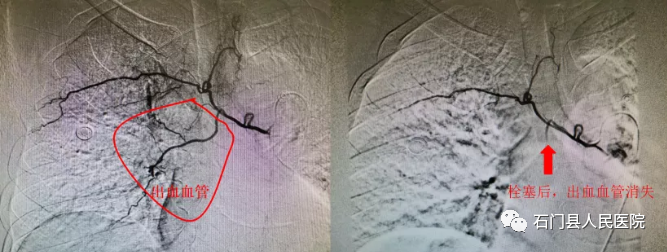

下肢动/静脉支架植入术、肾动脉支架植入术、肝/脾动脉栓塞术、下腔静脉滤器植入(取出)术,支气管动脉栓塞术,子宫动脉栓塞术。